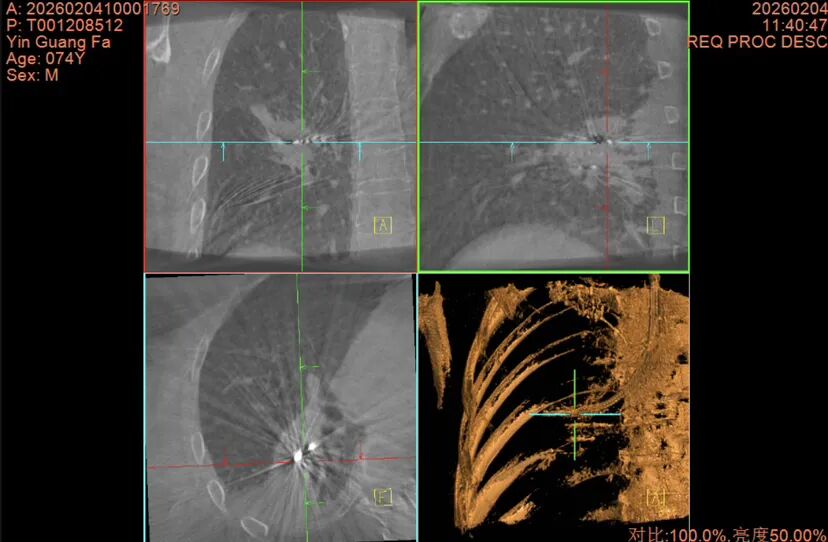

前Lung pro规划路径

术中C臂CT影像

术前,团队进行了充分的准备,用气道内的“GPS”虚拟导航系统(Lung pro)规划出抵达病灶的最优路径。

术中,团队在患者全麻插管状态下先行EBUS-TBNA,并通过现场细胞学评估排除淋巴结转移可能,同时取出组织送病理确诊,确认患者具有接受射频消融手术的指征。随后,团队使用细支气管镜经支气管建立肺实质抵达结节隧道,并经C臂CT及径向超声确认到达结节后,取材进行活检,经过现场细胞学评估结节为恶性细胞。组送病理再次确诊后,团队决定立即行射频消融,消融过程中利用C臂CT实时观察消融范围及探针位置。